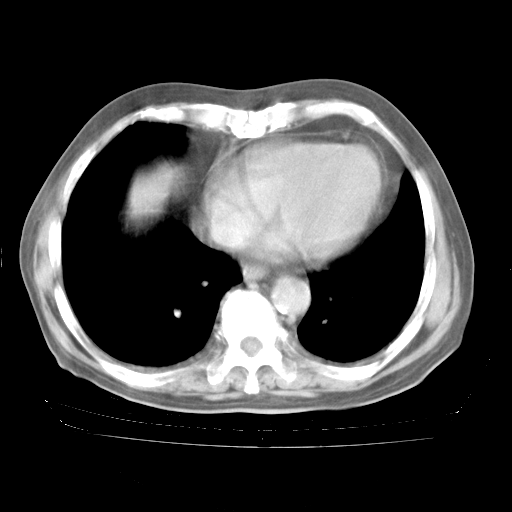

4月28日肺部CT——再次出现类似去年5月9日——透光度降低,“间质性”改变。

4月28日肺部CT